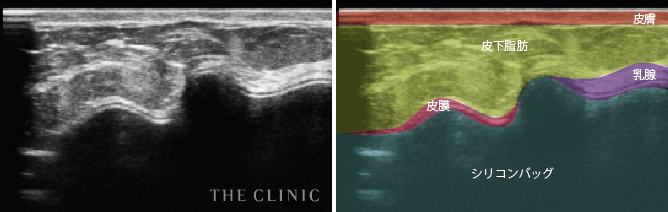

- シリコンバッグを包み込む被膜(カプセル)が厚くなり拘縮を起こしているため、バッグが変形しているのが確認できます。

シリコンバッグによるカプセル拘縮のエコー診断カルテ